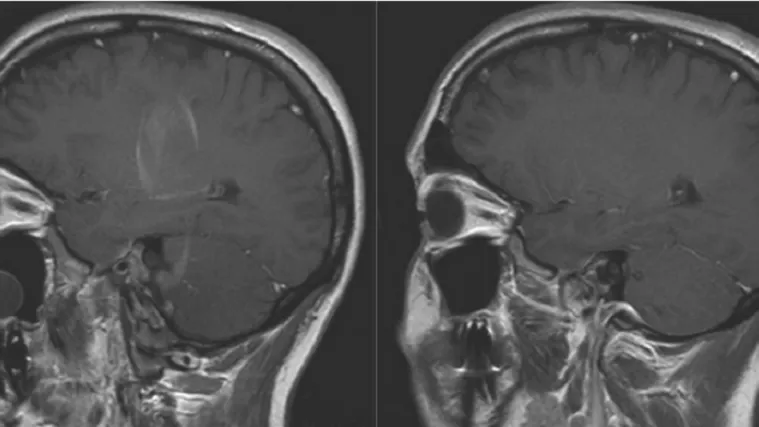

No što točno stres čini mozgu i kako se to mijenja vremenom i dalje je nepoznanica i predmet mnogih studija. Istraživanje Sveučilišta Yale pokazalo je kako stres smanjuje mozak, što je najizraženije kod centara koji kontroliraju osjećaje i metabolizam.

Kronični stres je, smatraju znanstvenici, opakiji od čak i od traume, a zbog centara na koje djeluje vodi zloupotrebi droga i rizičnom ponašanju.

Neurolozi Sveučilišta Berkeley iz Kalifornije dokazali su i da povećava rizik od mentalnih bolesti. Čak i slab, ali kroničan stres mijenja strukturu hipokampusa, dijela koji je ključan u obradi sjećanja i osjećaja. Hormoni poput kortizola i druge fiziološke reakcije remete ravnotežu stvaranja sive i bijele moždane tvari što mijenja način rada mozga.